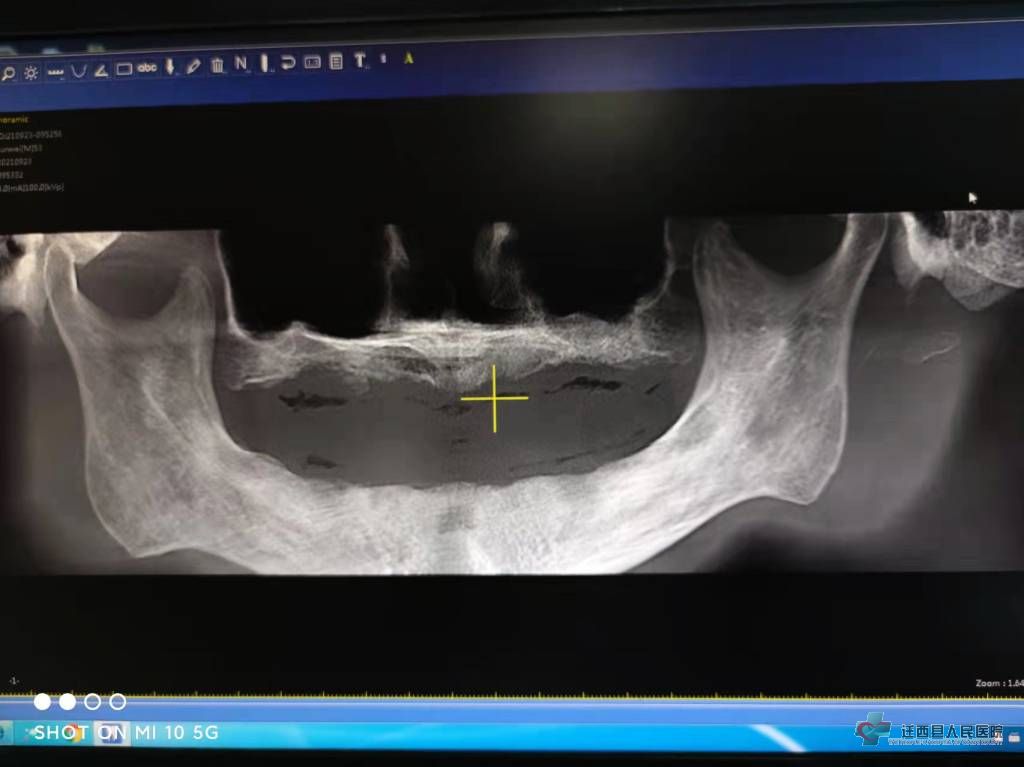

植入前CBCT